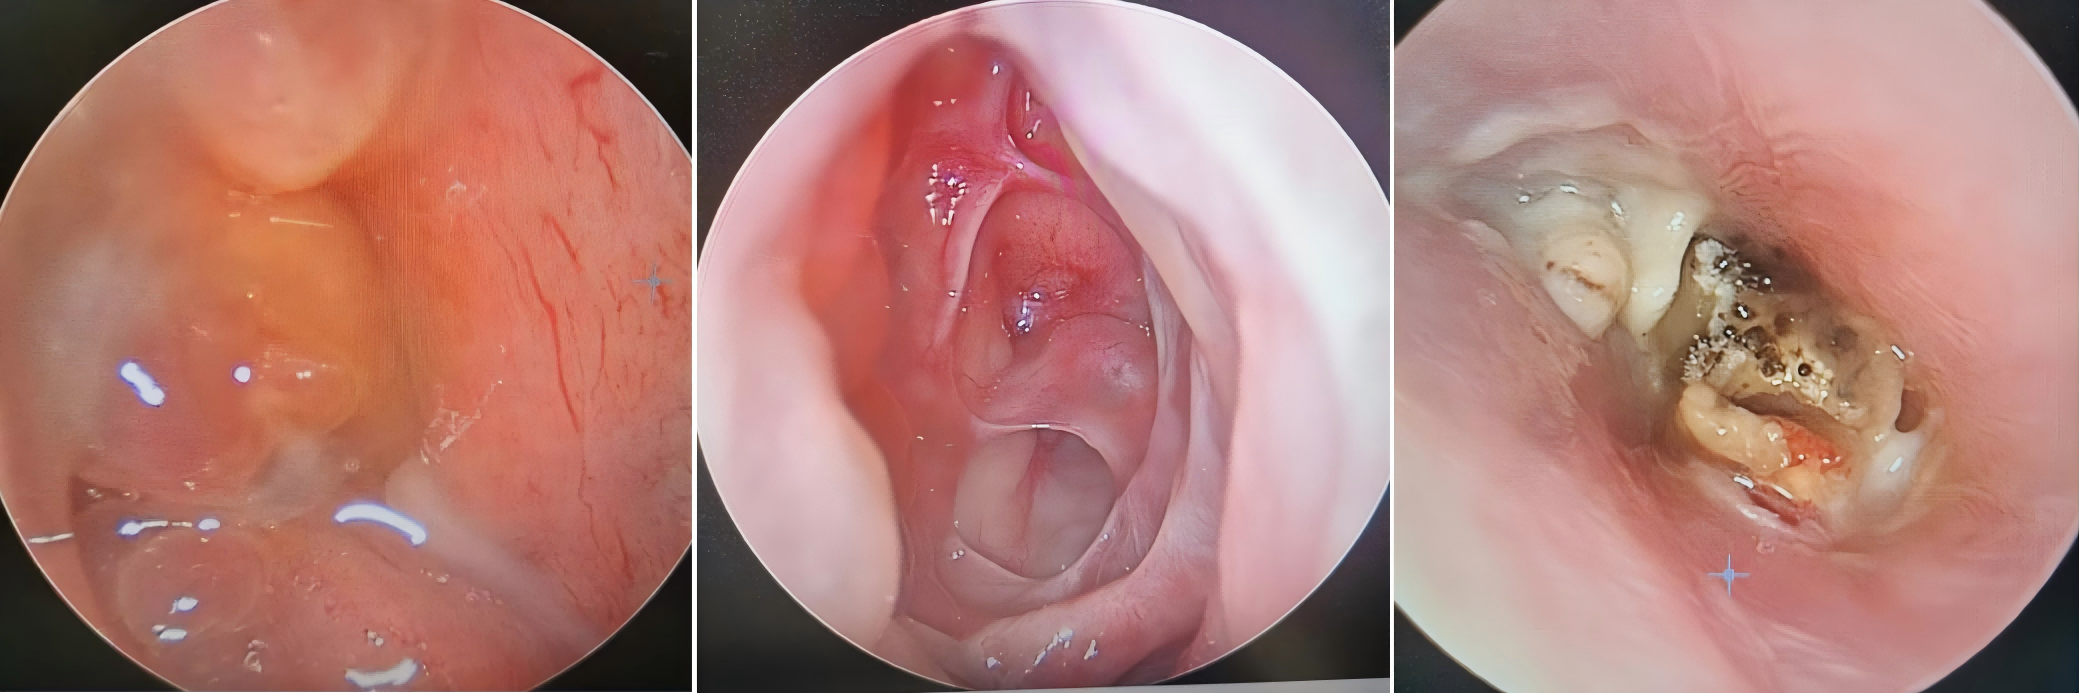

在霉菌性外耳道炎、鼻竇炎、扁桃體炎等疾病的診斷中,該系統(tǒng)能夠清晰地呈現(xiàn)出病變位置的病理組織結構,提供詳細的診斷信息,從而幫助醫(yī)生精準判斷病情。

醫(yī)用內(nèi)窺鏡攝像系統(tǒng)在微創(chuàng)手術治療領域扮演著至關重要的角色。以鼓膜穿刺、腺樣體肥大切除及鼻息肉摘除等復雜精細的內(nèi)鏡手術為例,該系統(tǒng)實時傳輸?shù)?/span>高清圖像為醫(yī)生的手術操作提供了精準指導,顯著提高了手術的精確度和安全性。

腺樣體肥大

臨床案例

江蘇省人民醫(yī)院  鼻中隔手術:視野清晰、損傷小合并癥少,既能徹底切除病變又能保留正常組織和結構